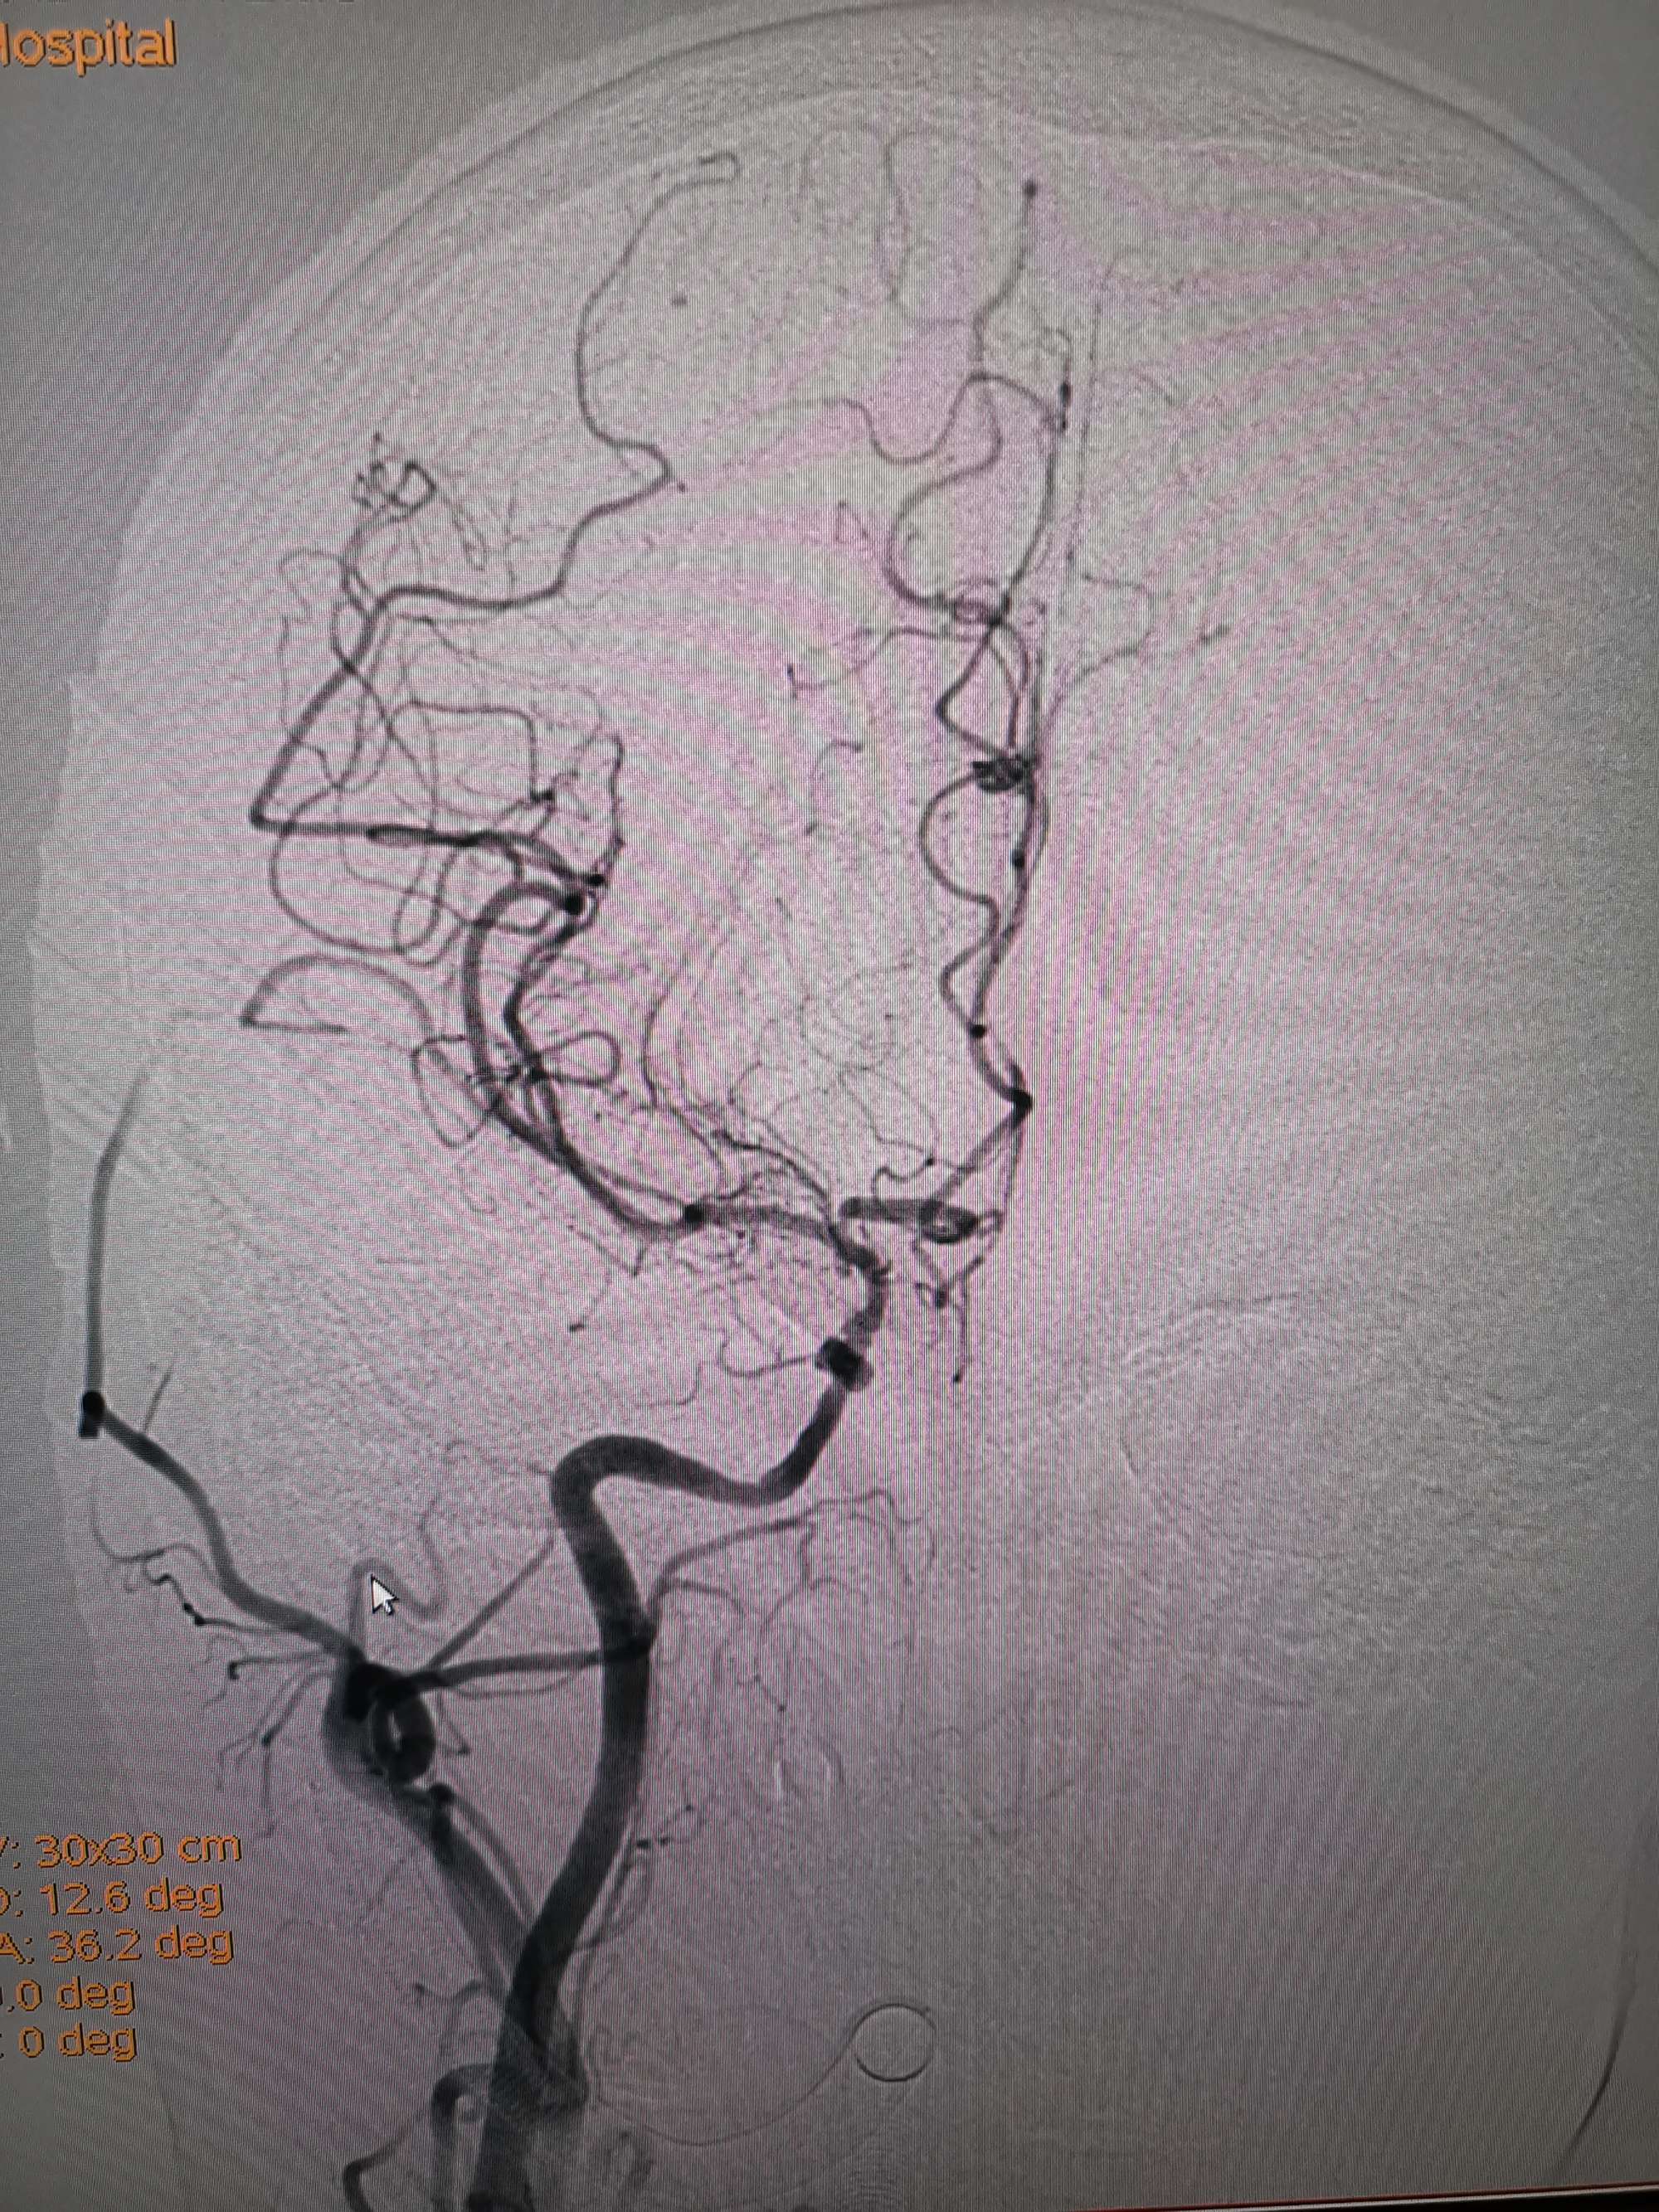

入院造影影像

术前再次造影评估

右侧椎动脉穿支供血及左侧PICA供血较入院时略有改善,但改善不明显。故按计划行左侧椎动脉再通术